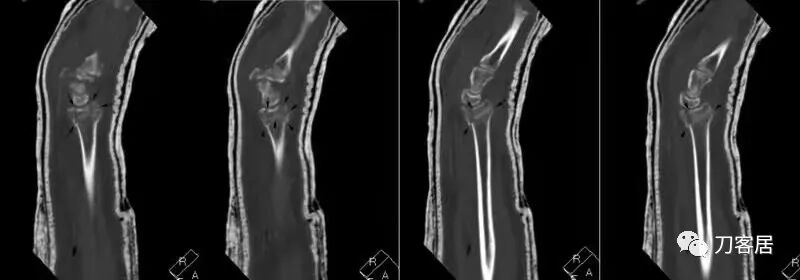

下面是这个6岁孩子,尺桡骨远端双骨折的术前及术后片子和外观照片。

1.  这是一个很简单的6岁儿童无移位的尺桡骨远端骨折。没有皮肤损伤,没有移位,没有骨折碎块儿。

2.  这个骨折处理起来也很简单,单纯的打石膏托或者中医的小夹板,或者正规的包括腕关节和肘关节的管型石膏外固定4周即可治愈该骨折。实在不行,如果这个孩子比较听话,不太调皮的话,用一本书,一个三角巾悬吊固定4周,都可以治愈该骨折。但是给这个患者用外固定架做了手术,而且桡骨远端的几颗克氏针距离骨折线太近,其中一枚克氏针进入到骨折间隙内。从这个术中图片来看,术者的外固定手术技术也有待于进一步的提高。毕竟术者应该还很年轻。从X线片来看,前臂及手的尺侧有不透光影,应该还使用了外固定石膏绷带托,而且我猜测应该是高分子的石膏绷带托,这个是纯属猜测,不一定是对的,不过如何解释前臂尺侧的不透光影呢?如果真是用了石膏绷带外固定的话,那为啥要做手术呢?外固定架术后就不该再用石膏绷带托辅助了。